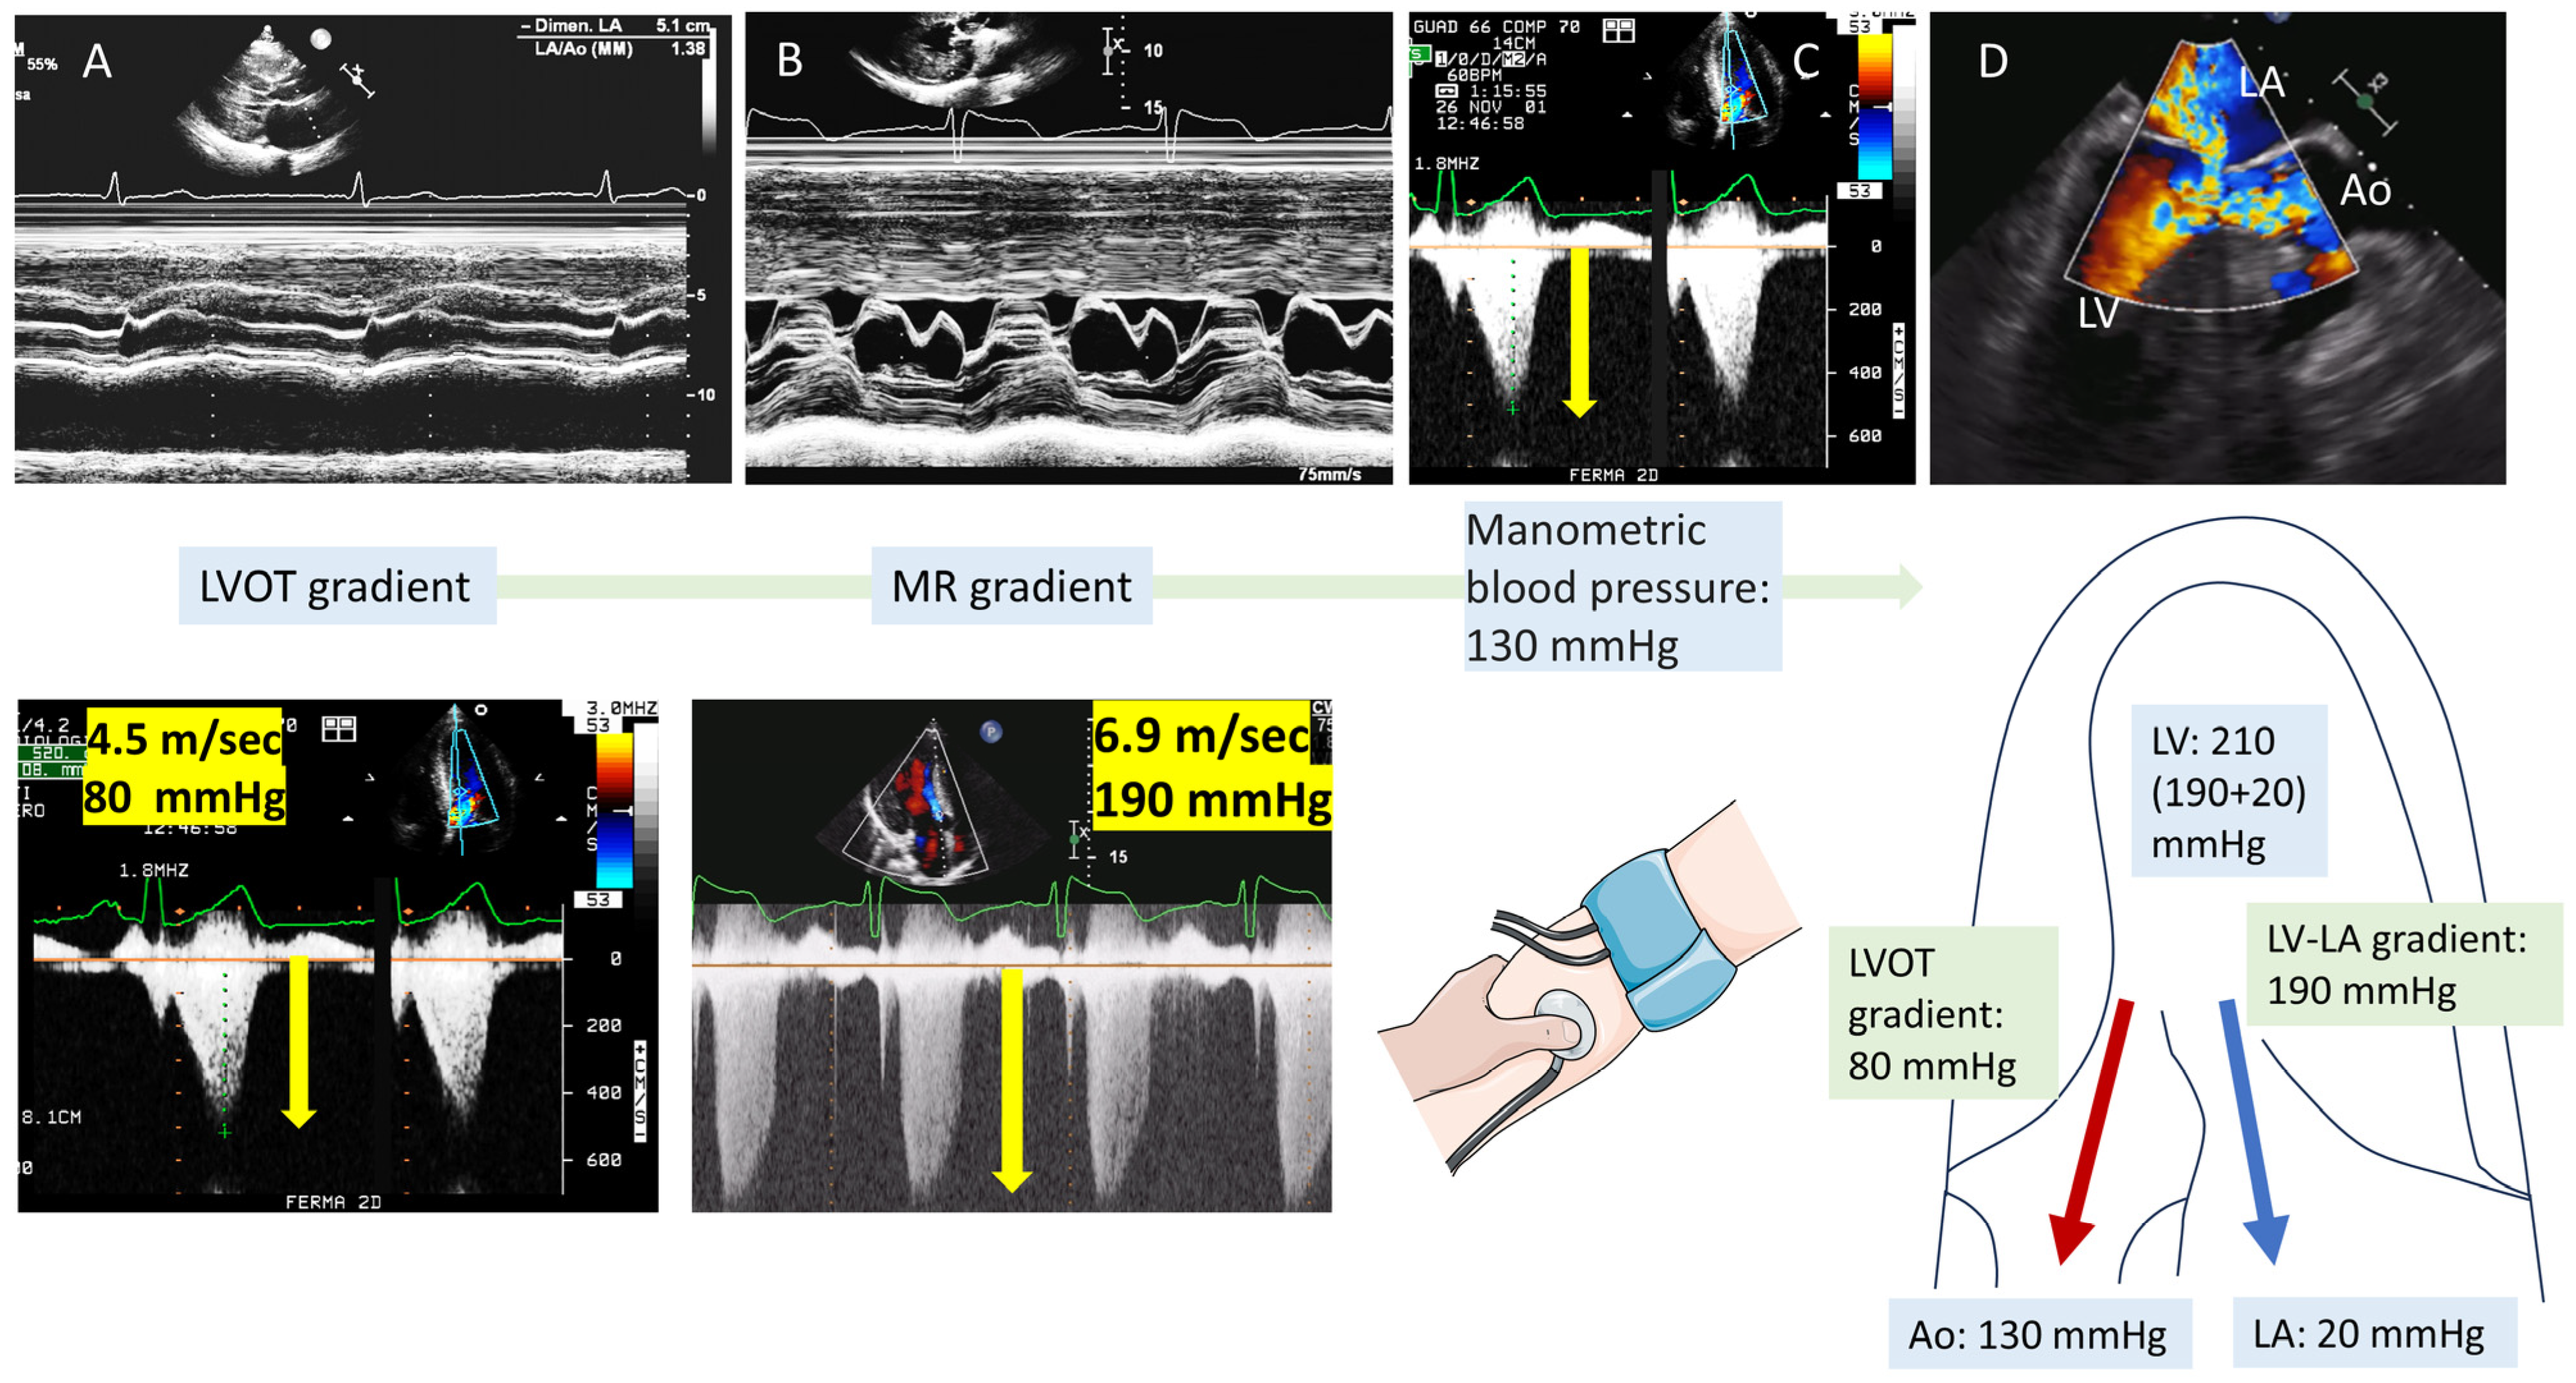

4. Tip and Tricks Concerning LVOT Obstruction Doppler Measurement

- Maron, M.S.; Olivotto, I.; Zenovich, A.G.; Link, M.S.; Pandian, N.G.; Kuvin, J.T.; Nistri, S.; Cecchi, F.; Udelson, J.E.; Maron, B.J. Hypertrophic cardiomyopathy is predominantly a disease of left ventricular outflow tract obstruction. Circulation 2006, 114, 2232–2239. [Google Scholar] [CrossRef]

- Nistri, S.; Olivotto, I.; Maron, M.S.; Grifoni, C.; Baldini, K.; Baldi, M.; Sgalambro, A.; Cecchi, F.; Maron, B.J. Timing and significance of exercise-induced left ventricular outflow tract pressure gradients in hypertrophic cardiomyopathy. Am. J. Cardiol. 2010, 106, 1301–1306. [Google Scholar] [CrossRef]

- Olivotto, I.; Cecchi, F.; Poggesi, C.; Yacoub, M.H. Patterns of disease progression in hypertrophic cardiomyopathy an individualized approach to clinical staging. Circ. Heart Fail. 2012, 5, 535–546. [Google Scholar] [CrossRef]

- Maron, M.S.; Olivotto, I.; Betocchi, S.; Casey, S.A.; Lesser, J.R.; Losi, M.A.; Cecchi, F.; Maron, B.J. Effect of Left Ventricular Outflow Tract Obstruction on Clinical Outcome in Hypertrophic Cardiomyopathy. N. Engl. J. Med. 2003, 348, 295–303. [Google Scholar] [CrossRef]